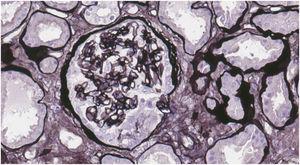

Case reportWe present the case of a 19-year-old male, an active smoker with a history of attention deficit hyperactivity disorder. He consulted the Hospital Emergency Service in August 2017 with a one-week history of coughing and dyspnoea. On physical examination he present crackles in both lungs and chest X-ray showed bilateral interstitial infiltrates. He was admitted with suspected bilateral pneumonia. At 48h, he had a progressive decrease in diuresis and haemoptysis. Arterial blood gases showed respiratory failure, for which he required orotracheal intubation with invasive mechanical ventilation and he was transfered to the Intensive Care Unit (ICU). Blood tests showed haemoglobin 8.6mg/dl, creatinine 4.35mg/dl and urea 250mg/dl. Urinalysis showed macrohaematuria and protein/creatinine ratio 3.5g/g. We requested a glomerular study which was negative for anti-GBM antibodies, with all other findings being normal or negative (complement, immunoglobulins, proteins, antinuclear antibodies [ANA], antineutrophil cytoplasmic antibodies [ANCA] and serology for human immunodeficiency virus [HIV], hepatitis B virus [HBV] and hepatitis C virus [HCV]). Fibre-optic bronchoscopy was performed and the findings were consistent with alveolar haemorrhage, diagnosing pulmonary renal syndrome. We started immunosuppressive therapy with intravenous boluses of methylprednisolone 1g a day for three consecutive days, and oral prednisone 1mg/kg/day, intravenous cyclophosphamide every three weeks, dose adjusted to glomerular filtration rate (GFR), plasma exchange (16 sessions in total), and renal replacement therapy with haemodialysis was required. A renal biopsy was performed after discharge from ICU once the patient was stabilised. Optical microscopy showed 28 glomeruli, none of them sclerosed. A circumferential epithelial crescent was detected in one of them (Fig. 1). Direct immunofluorescence showed an intense positive linear pattern for IgG, Kappa and Lambda, and mesangial and parietal granular pattern for C3 (Fig. 2). Occasional reduplications of the basement membrane of nonspecific appearance were observed on electron microscopy. With these findings, anti-GBM disease was diagnosed. After several weeks of hospitalisation, the patient developed a number of complications, including secondary gastrointestinal infection due to cytomegalovirus, and severe leucopenia, for which cyclophosphamide was switched to rituximab. He had two doses of 375mg/m2/week, but after another episode of alveolar haemorrhage, induction treatment with cyclophosphamide was completed. He received a total of six cycles of cyclophosphamide (total dose 6200mg), with remission of the signs and symptoms and laboratory abnormalities, and he recovered normal renal function which is maintained.